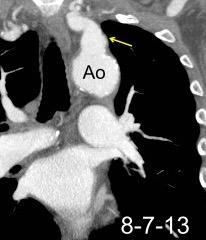

“Draped aorta”.

Indica rotura aórtica reciente. Se manifiesta por una pared aórtica posterior o el contacto con el borde lateral vertebral borrados por la hemorragia.

Rotura aneurisma de Aorta descendente.

Dolor. (10 días antes: "Rotura inminente”)